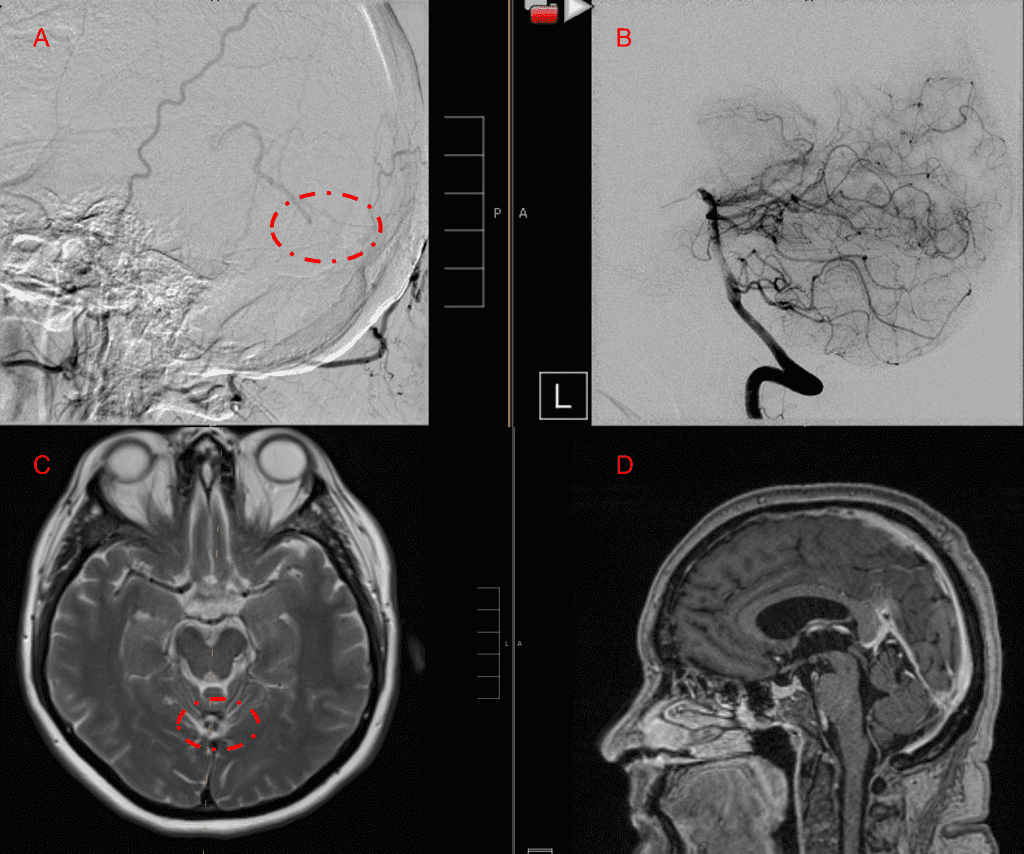

Embolization was successful at immediately reducing the pressure into the Aneurysmal Varix with greater than 90% reduction in A-V shunts. After an intensive period of critical care monitoring and care for her initial brain hemorrhage, she made a near complete recovery with mild intermittent left sided paresthesias and generalized deconditioning. After receiving inpatient and outpatient Acute Rehabilitation, Physical, and Occupational therapy, she completely recovered all of her Activities of Daily Living (ADLs) at 3 months and achieved an modified Rankin Scale (mRS) of 0. On follow-up angiography, small residual low flow A-V shunts were identified and targeted for Gamma Knife Radiosurgery (Figure 5 and 6).

Figure 5. Bilateral ECA Lateral angiograms (A and B) demonstrates small residual indirect supply To the AVM from the bilateral Occipital arteries.

Figure 6. MRI and Catheter Angiograms precisely localize the residual A-V shunts vessels to perform Gamma-Knife Radiosurgery to deliver therapeutic doses to the targets.